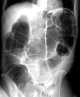

Volvulus

A volvulus is when a loop of intestine twists around itself and the mesentery that supports it, resulting in a bowel obstruction. Symptoms include abdominal pain, abdominal bloating, vomiting, constipation, and bloody stool. [Source: Wikipedia ]